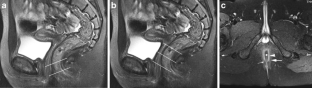

Perianal complications of Crohn disease are a common occurrence in children and can result in significant morbidity when not accurately characterized prior to surgical intervention. MRI is an excellent imaging modality for the evaluation of perianal inflammatory bowel disease – allowing characterization and detailed description of perianal fistulas. MRI has many advantages over other imaging modalities for the pediatric patient. Radiologists will benefit from a sophisticated understanding of perianal anatomy, the classification of perianal fistulas, the advantages MRI offers in characterization of perianal fistulas as well as the common and incidental findings that are important in the MRI evaluation of perianal inflammatory bowel disease in children. Perianal fistulas are found at a high rate in pediatric referrals and are more commonly found in male patients.

Fig. 2